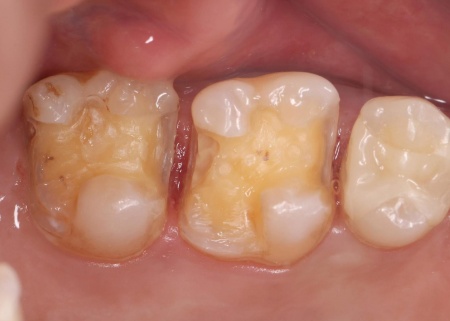

40代女性 金属アレルギーを発症した患者様のメタルインレーを除去し非金属の素材で修復した症例

患者様には、まず皮膚科での金属アレルギー検査をおすすめしたところ、歯科治療で使用していた金属がアレルギーの原因と判明しました。

患者様の口腔内には、金属素材で修復が行われている部位があり、これが体調不良につながっていたと考えられます。

以上のことから、口腔内の金属をすべて除去し、金属を使わない材料で修復する必要があると診断しました。

患者様は噛む力が非常に強く、その影響でエナメル質が割れてしまっています。

そこで詰め物の素材には、自費診療の白い素材「セラミック」の中でも、人工ダイヤモンドと呼ばれるほど強度があり、審美性にも優れている「ジルコニア」を選択しました。

そのため、噛み合わせが強くかかる歯のみジルコニアで作製し、ほかの歯は強度の面でジルコニアには劣るものの、保険診療で非金属の白い素材「CAD/CAM冠」で作製することを提案し、同意いただきました。

詰め物の形状には、歯の溝や一部を補う小さな詰め物「インレー」と、歯の噛む面を広範囲で覆う「アンレー」があります。

今回は、もともと装着されている金属の詰め物(メタルインレー)を除去し、その部位に合った形状の詰め物を都度選択することにしました。

まずはメタルインレーをすべて外し、詰め物を装着するために歯の形を整え、型取りを行います。

後日、完成した詰め物を装着し、歯にぴったりと合っているか、噛み合わせに問題がないかを十分に確認して、治療を終了しました。